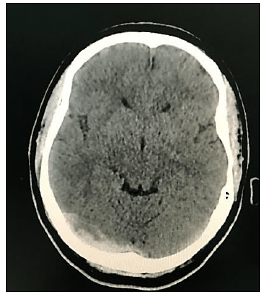

“Paciente, sexo feminino, 40 anos de idade, tabagista ativa, teve quadro de Covid-19 leve há uma semana, evoluindo com cefaleia holocraniana persistente, de forte intensidade, refratária à analgesia simples. Nega ter cefaleia prévia. Após três dias de dor, cursou com um episódio de crise convulsiva generalizada, sendo, então, levada ao hospital de referência próximo a sua residência, onde realizou a seguinte tomografia computadorizada de crânio sem contraste:”